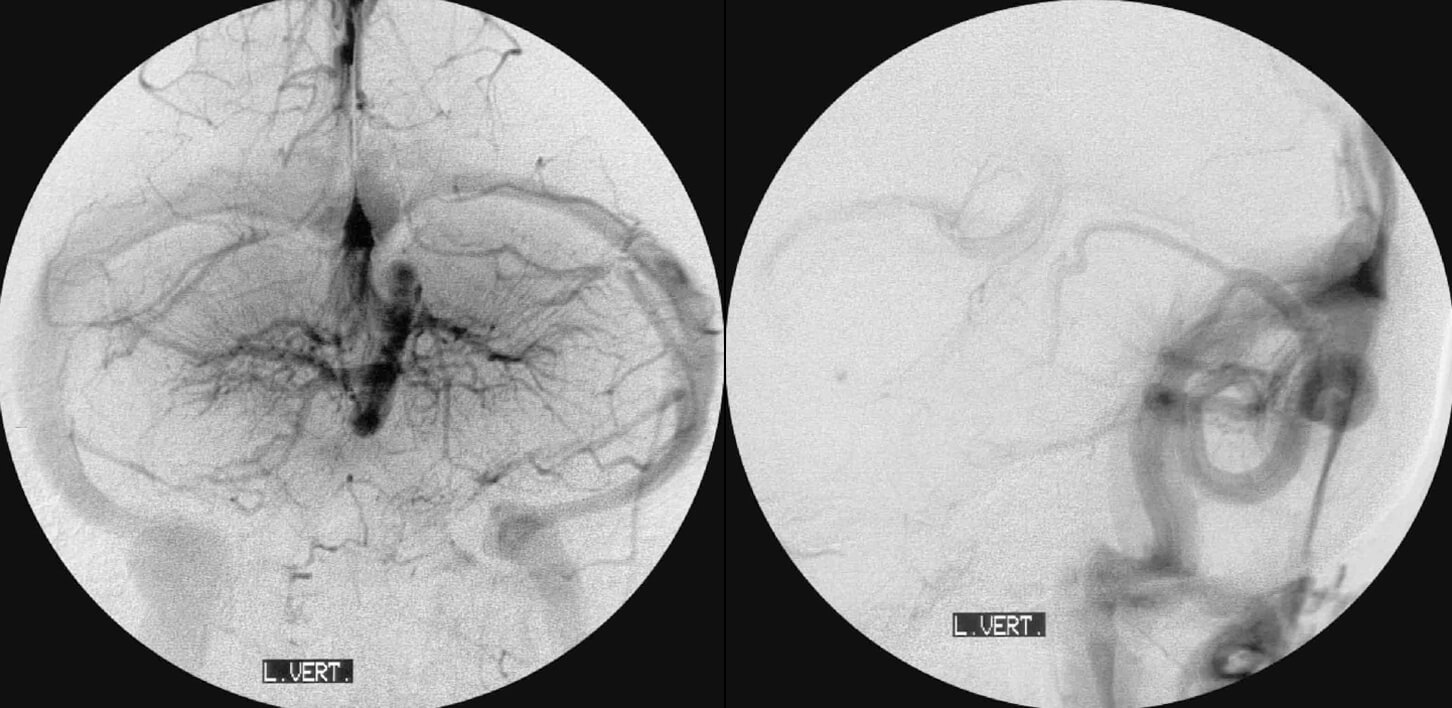

Παριστούν τις ακραίες εκφάνσεις του αναστομωτικού, μυελικού φλεβικού δικτύου.

Επιπολής, όπου μυελικές φλέβες διασχίζουν την λευκή ουσία (trancerebral medullary veins) και παροχετεύουν εν τω βάθει υποεπενδυματικές περιοχές προς φλοιώδεις φλέβες ατην επιφάνεια του εγκεφάλου

Εν τώ βάθει, όπου υποφλοιώδεις περιοχές της λευκής ουσίας παροχετεύονται φλεβικά προς εν τω βάθει, υποεπενδυματικούς φλεβικούς συλλέκτες.

Αποτελούν μη παθολογικό φλεβικό πρότυπο, συμβατό μέ φυσιολογική λειτουργία (ανωμαλίες και όχι δυσπλασίες). Παροχετεύουν φυσιολογικό παρέγχυμα και δέν πρέπει νά αφαιρούνται χειρουργικά ή νά θεραπεύονται μέ στερεοτακτική ακτινοθεραπεία.

Συχνά συνυπάρχουν μέ τα λεγόμενα σηραγγώδη αιμαγγειώματα

που στην πραγματικότητα παριστούν φλεβικές δυσπλασίες (δεν είναι αιμαγγειώματα). Συνεπώς, σε κάθε αιμορραγία όπου ανευρίσκεται DVA, πρέπει να αποκλείεται συνύπαρξη σηραγγώδους τύπου φλεβικής δυσπλασίας ή αρτηριοφλεβώδης επικοινωνία.